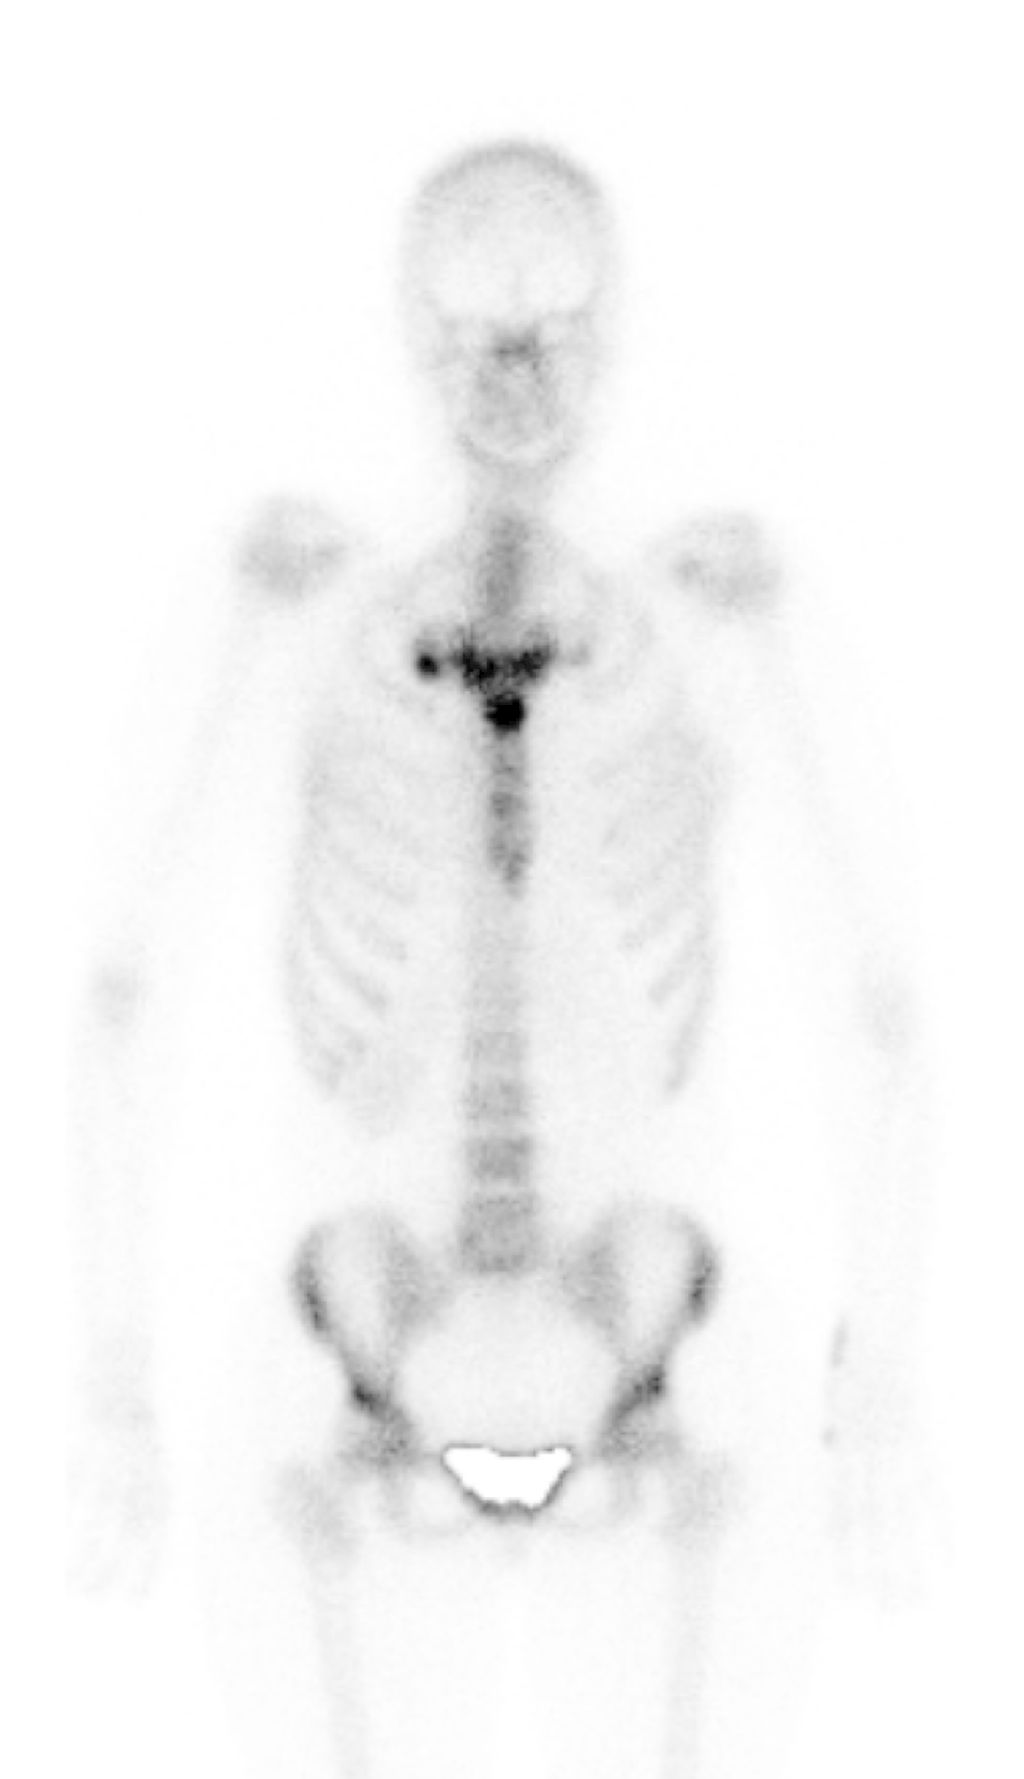

Abb. 5: Skelettszintigrafie mit deutlicher Tracer-Anreicherung im sternocostoclavikulären Übergangsbereich

Eine junge Patientin mit Psoriasis wurde wegen diffuser Gelenksbeschwerden zur Skelettszintigrafie zugewiesen. Hier zeigte sich neben geringen Aktivitäten in den Fingergelenken eine auffällige Anreicherung im Bereich der Sternocostoclavikulargelenke (Abb. 5), korrespondierend mit der Klinik, die als posttraumatisch gedeutet wurde. Allerdings war anamnestisch kein Trauma erhebbar.

Zur genaueren Abklärung wurde eine CT durchgeführt. Dabei zeigten sich deutliche erosive Veränderungen, jedoch kein Hinweis auf eine Fraktur (Abb. 6). In Zusammenschau mit der Klinik bei zusätzlich vorliegenden Hautveränderungen palmar und plantar wurde die Diagnose eines SAPHO-Syndroms (Synovitis, Akne, Pustulosis, Hyperostosis und Osteitis), einer Form der seronegativen Spondylarthritiden, gestellt.